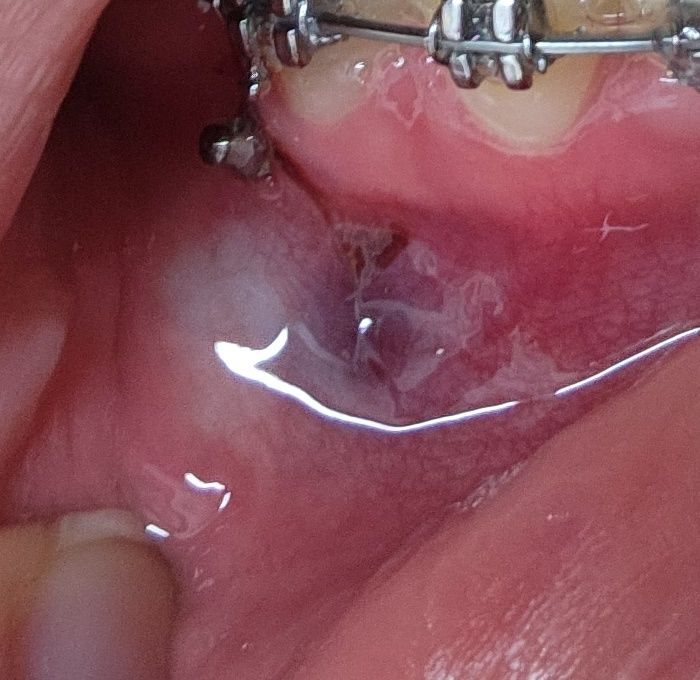

스크류 교정 후 잇몸에 안쪽에 새까만 피가 맺혔습니다

오늘 스크류 나사 아래쪽에 3개를 박았는데요, 의사가 왼쪽에 박은 나사가 3번 치아에 가까운데 아프지 않냐고 말했습니다. 당연히 심는 중에 아파서 마취를 2번이나 했으니 잘 모르겠더라고요. 근데 집에 돌아오면서부터 너무 아팠습니다.. 거울을 보니 스크류 밑으로 인접한 치아들 잇몸 안쪽이 새까맣게 피가 고여있고요 이거 괜찮은 건가요? 피가 고이는 것도 흔한 일인가요? 다른 스크류 심었을 때는 이런 일이 없었습니다

사진에 보이는 교정장치 들이 잇몸을 계속 자극해서 생긴거 같습니다. 많이 아프시면 약을 드시고 상처는 시간이 지나면 괜찮아 지실꺼에요.

스크류를 식립하는 도중 점막 조직안에 출혈이 생기게 되면 사진과 같이 혈액이 점막내에 찰수 있습니다.

출혈이 된 부위는 시간이 지나면서 점차 아물게 되며 통증이 심하다면 타이레놀과 같은 간단한 진통제를 복용하는것이 좋습니다.

피가 고이는 증상은 나타날 수 있습니다 다만 통증이 계속해서 심하다면 염증 가능성이 있습니다.